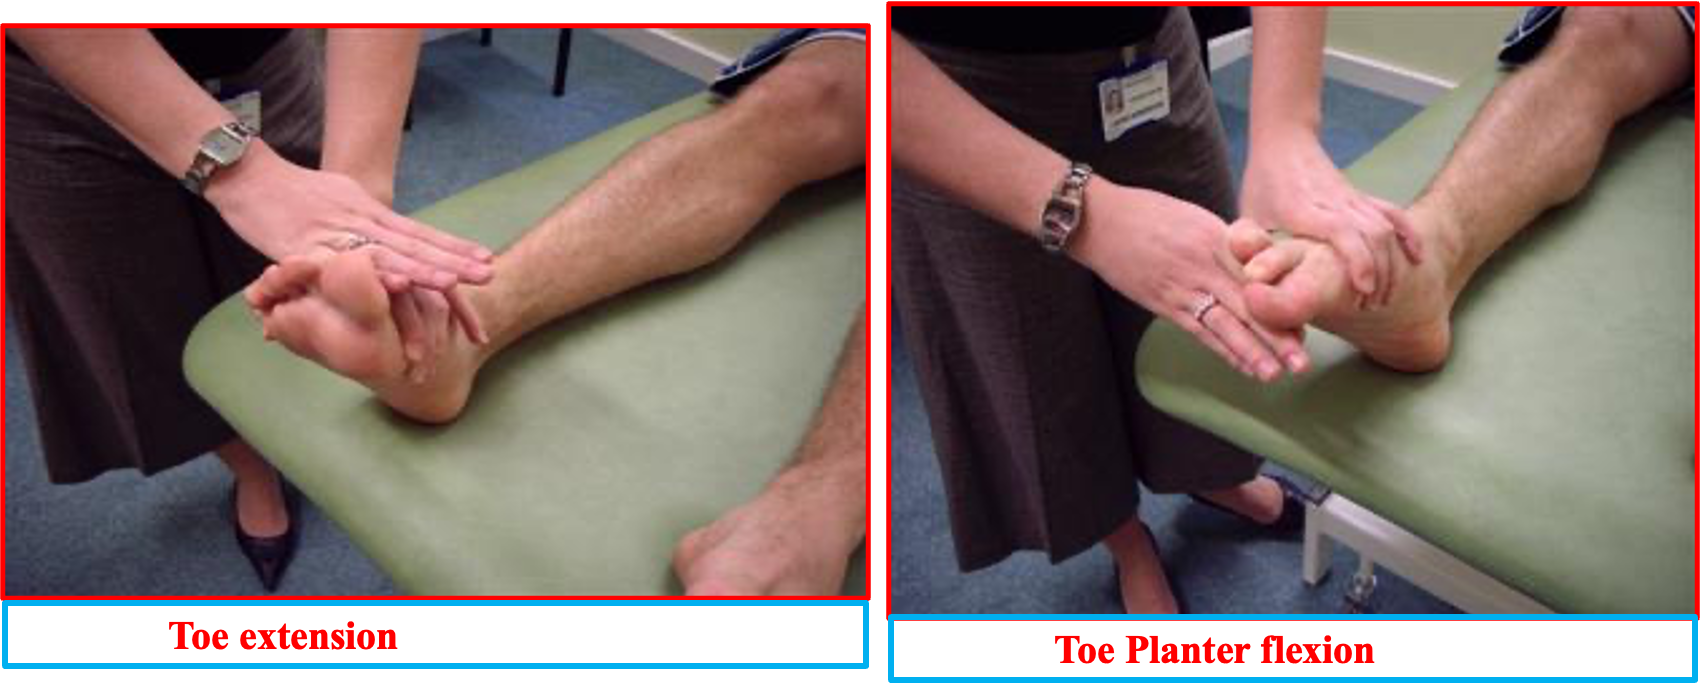

Toe extention and flexion power assessment)

Toe extension involves extending the toes away the sole of the foot. The muscle of the toe extension is extensor digitorum longus, and the intrinsic foot muscles.

Toe flexion involves bending the toes towards the sole of the foot. The muscle and tendon involved in toe flexion is flexor digitorum longus and intrinsic foot muscles.